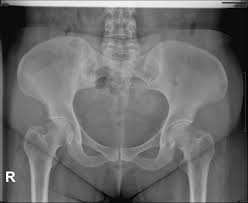

고관절 통증이 나타나는 위치

고관절 통증은 엉덩이 깊숙한 부위에서만 느껴진다고 생각하기 쉽지만, 실제로는 다양한 위치로 퍼져 나타날 수 있습니다.

• 사타구니 안쪽 통증

• 엉덩이 한쪽 깊은 통증

• 허벅지 앞쪽 또는 옆쪽 통증

• 무릎까지 이어지는 불편감

특히 사타구니 통증은 고관절 이상을 가장 강하게 의심할 수 있는 신호로 전문가들도 중요하게 보는 증상입니다.